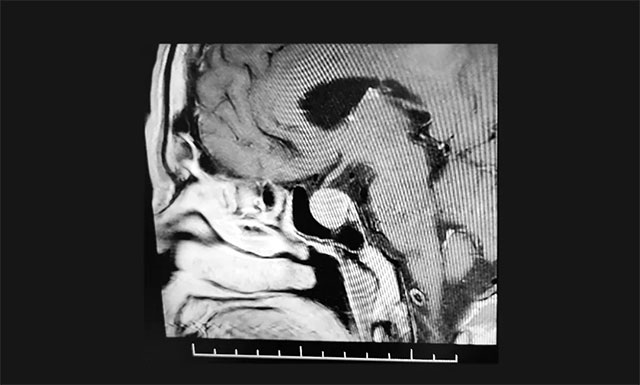

▲ 影像檢查顯示:垂體大腺瘤,超蝶鞍生長

鞍區(qū)MRI增強提示:蝶鞍顯著擴大,鞍區(qū)(偏左側)見一實性腫塊影,超蝶鞍生長,左側腫塊矢橫高徑約1.8*1.5*1.8cm。病變向鞍上生長,突入鞍上池,輕度推移視神經(jīng)左側份。鞍底受壓變薄下陷,左側鞍旁海綿竇受侵、外移,血管(頸內A)包繞約1/3以上。

結合病史、影像等,神經(jīng)外科6B病區(qū)潘仁龍主任、李士其教授、吳治群博士會診后考慮為生長激素垂體腺瘤,正是垂體瘤導致張老伯面容改變、肢端粗大等。手術指征明確,應盡快手術治療。